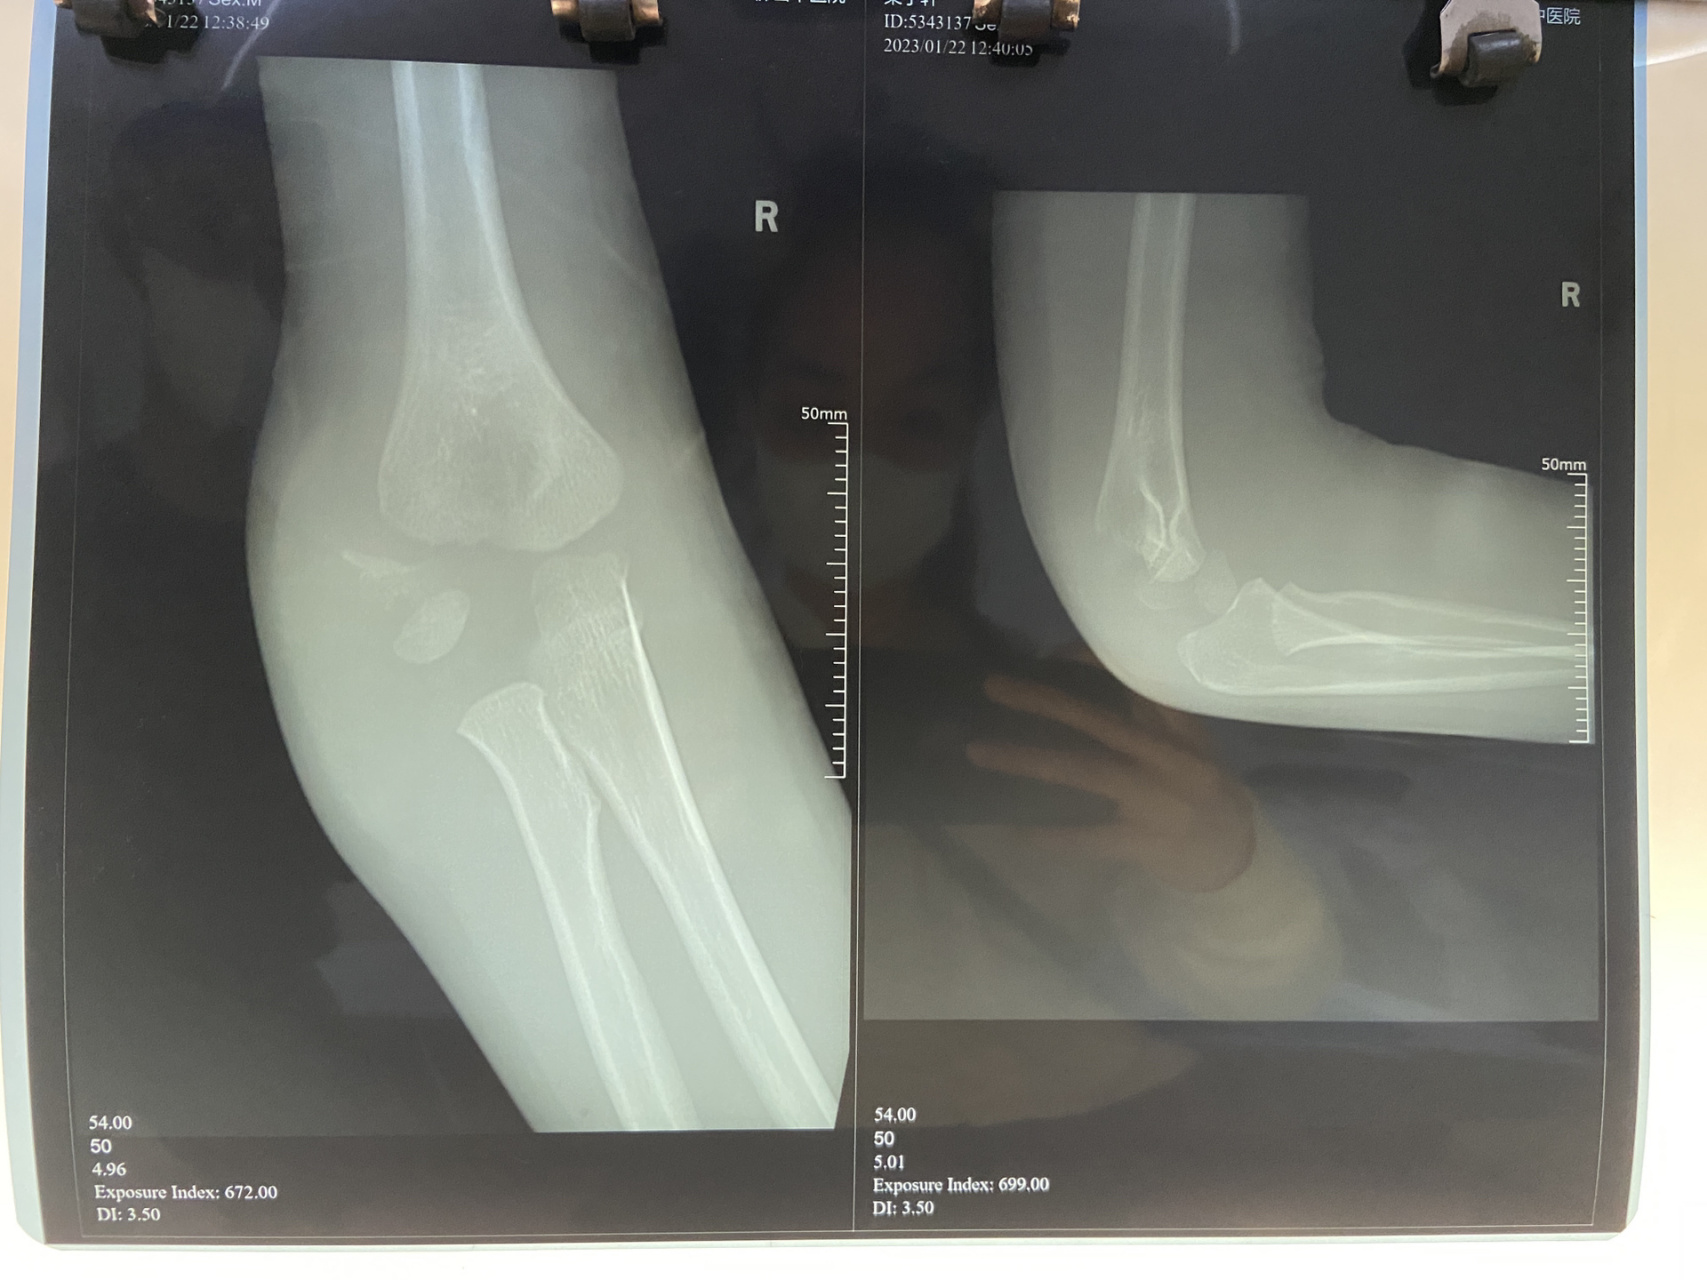

新年第一例肱骨髁上骨折

图片尺寸1840x4096